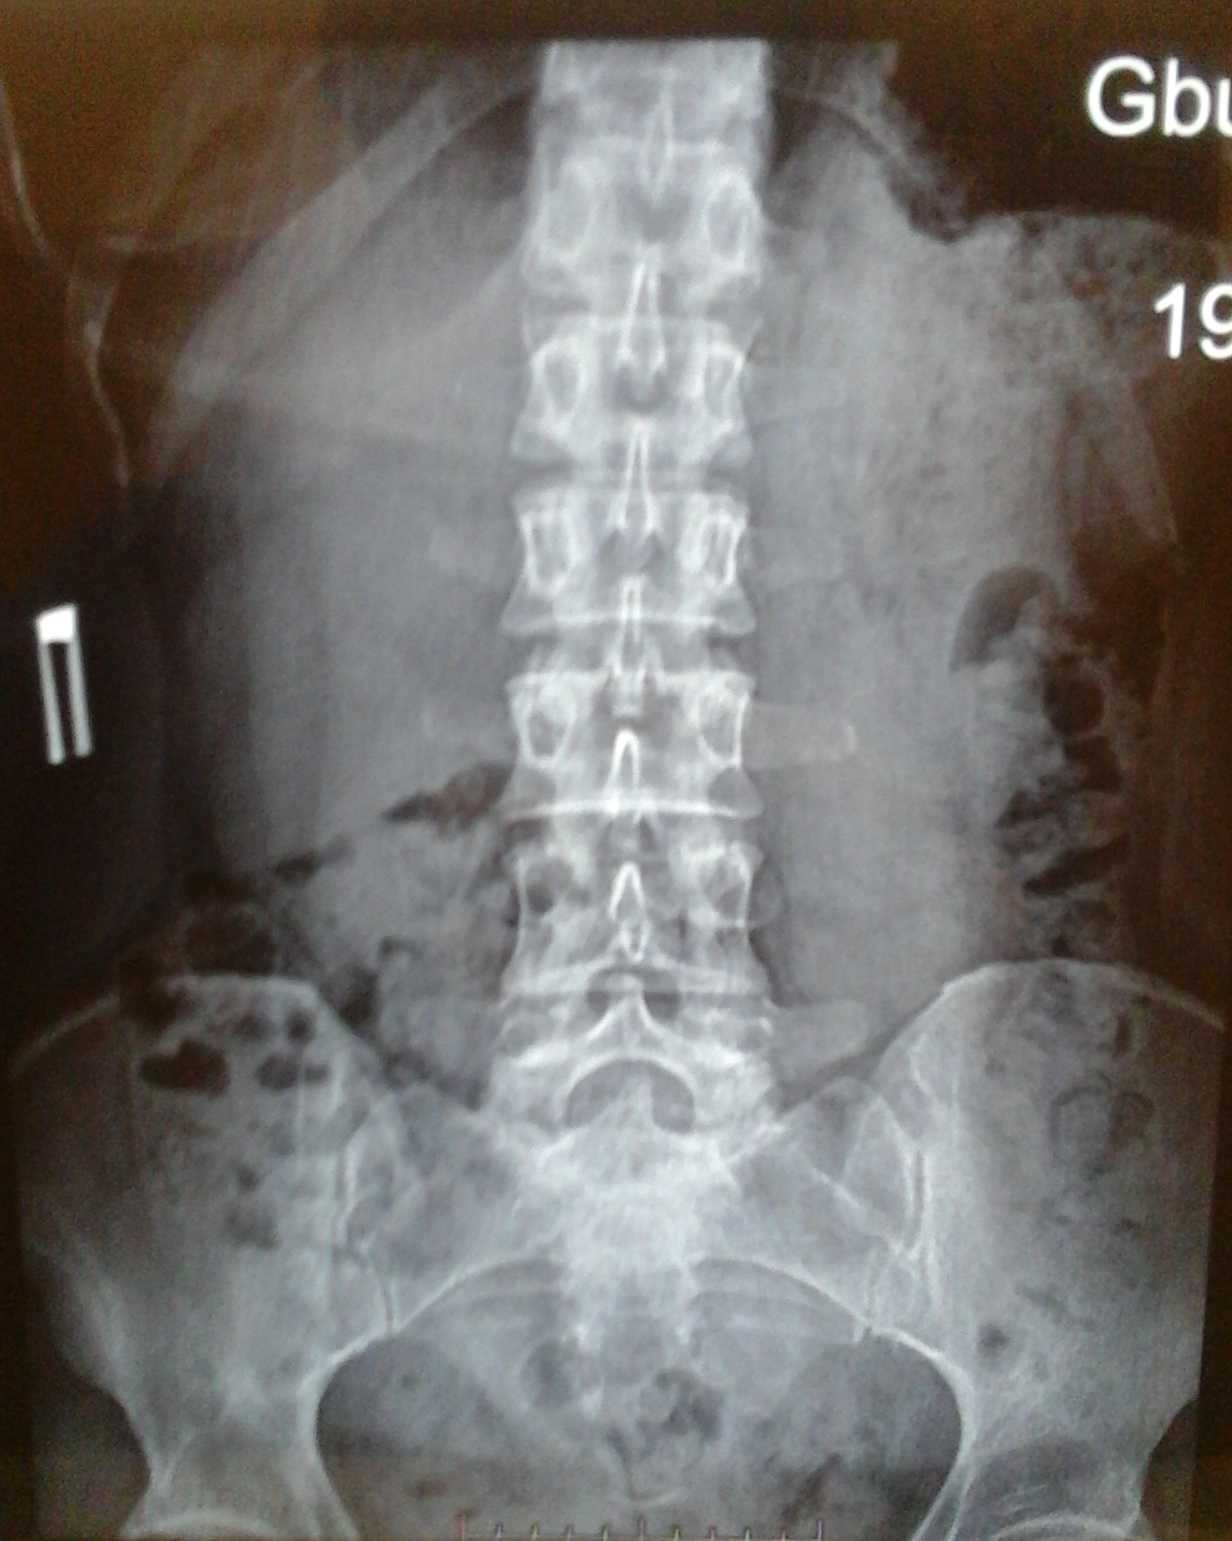

Рентгеновские снимки крестцово-копчикового отдела позвоночника